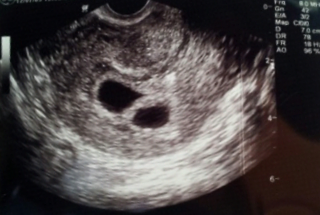

그것도 쌍둥이에요. 의사쌤께서 초음파 보시다가 어?둘이네~ 하셔서 정말 놀랬어욯ㅎ

지금 임신5주차 입니다. 한달 전 글을 쓸때도 전 임신 중이었던 거에요!!!